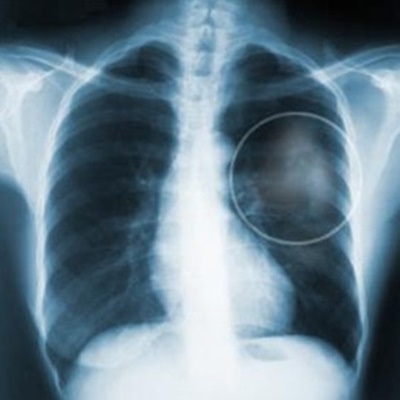

폐암 증상

폐암의 증상으로는 호흡곤란이 나타납니다. 폐암에 걸리게 되면숨이 차게될 수 있다는 경우가 많아해 질 것이다. 큰 불편이 없는 것이다고 무시하지 말고 장기간 증상이 계속되면 반드시 진찰을 받아보는 것이 좋아합니다.

갑자기 기침이 심해지어야 하거나 피가 섞인 가래가 나오면 폐암을 의심해야 합니다. 폐암초기에는 신체를 통해 별 다른 증상이 없으므로 간과하고 넘어가기 쉬운데요. 증상이 계속되면 병원에가서 진찰을 받는 것이 폐암을 조기발견할수 있는 방법인 것입니다.